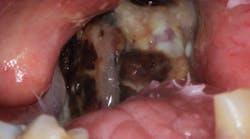

After recovering from that introduction, it turns out that this 71-year-old gentleman was diagnosed with and has been treated for tonsillar cancer that had spread almost to his entire head-and-neck area. The cancer was supposedly gone in 2012 with radiation and chemotherapy, but as karma would have it, it returned with a vengeance (see photo), and the prognosis is not good. Despite this, his chief complaint was just that he wanted to chew his food better. That’s it. So in order to help him achieve this goal, I’m going to go against all the rules of dentistry to get him to a state that at least improves his status quo.

You see, this patient has a full upper denture, broken carious teeth on the lower, and he is not a candidate for extractions due to the high risk for osteoradionecrosis. He also opens only two inches, which makes restorative work nearly impossible. What would you do?